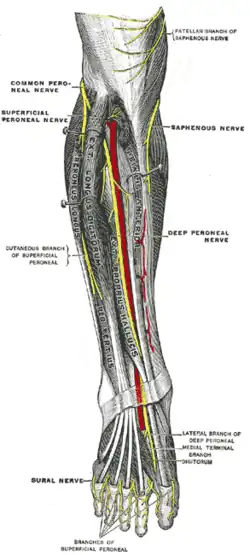

Deep nerves of the front of the leg Back of left lower extremity

Back of left lower extremity Lateral aspect of right leg